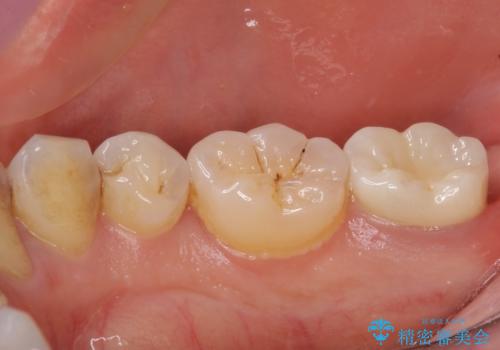

- 根管治療の専門医院で根管治療を行った後、セラミッククラウンによる補綴治療を希望して来院された患者様です。

根管治療後の土台も構築されていたので、仮歯に置き換えた後にフルジルコニアクラウンにて補綴することとしました。